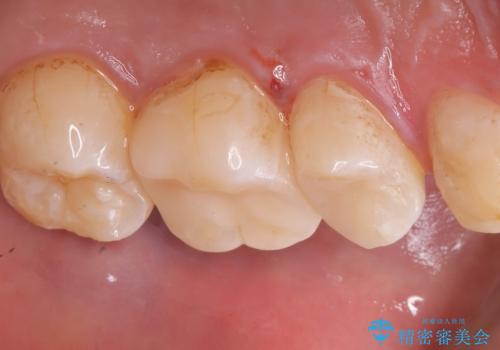

左上5番目の歯の側面に実質欠損を認め、隣の6番目の歯にも虫歯を認めたため両歯ともセラミックインレーでの治療となりました。

左上5番遠心に実質欠損を認め、さらに5番と6番の隣接面にもカリエスを認めました。6番の咬合面には、元々コンポジットレジン修復が施されており、劣化がみられたのでその部分も含め修復することとなりました。

セラミックインレーセット時は、ラバーダム防湿を行っています。